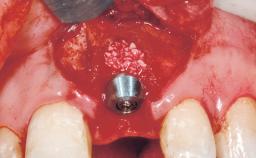

Late Placement of an Implant in a Maxillary Left Central Incisor Site

A 36-year-old female patient was referred for the replacement of the upper left central incisor (tooth 21), which had fractured. Although the tooth had been asymptomatic for many years, the crown began to loosen, at which time she presented to her dentist for an assessment. Teeth 21 and 22 had both been endodontically treated many years previously. She was a healthy individual and a non-smoker.

Type of Implants Two-Piece

Bone Augmentation Horizontal|Staged

Bone Volume Deficient horizontally, requiring prior grafting